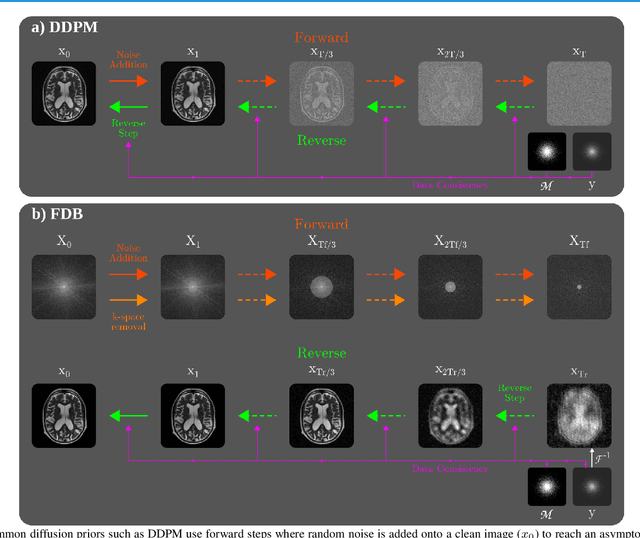

Abstract:Recent years have witnessed a surge in deep generative models for accelerated MRI reconstruction. Diffusion priors in particular have gained traction with their superior representational fidelity and diversity. Instead of the target transformation from undersampled to fully-sampled data, common diffusion priors are trained to learn a multi-step transformation from Gaussian noise onto fully-sampled data. During inference, data-fidelity projections are injected in between reverse diffusion steps to reach a compromise solution within the span of both the diffusion prior and the imaging operator. Unfortunately, suboptimal solutions can arise as the normality assumption of the diffusion prior causes divergence between learned and target transformations. To address this limitation, here we introduce the first diffusion bridge for accelerated MRI reconstruction. The proposed Fourier-constrained diffusion bridge (FDB) leverages a generalized process to transform between undersampled and fully-sampled data via random noise addition and random frequency removal as degradation operators. Unlike common diffusion priors that use an asymptotic endpoint based on Gaussian noise, FDB captures a transformation between finite endpoints where the initial endpoint is based on moderate degradation of fully-sampled data. Demonstrations on brain MRI indicate that FDB outperforms state-of-the-art reconstruction methods including conventional diffusion priors.